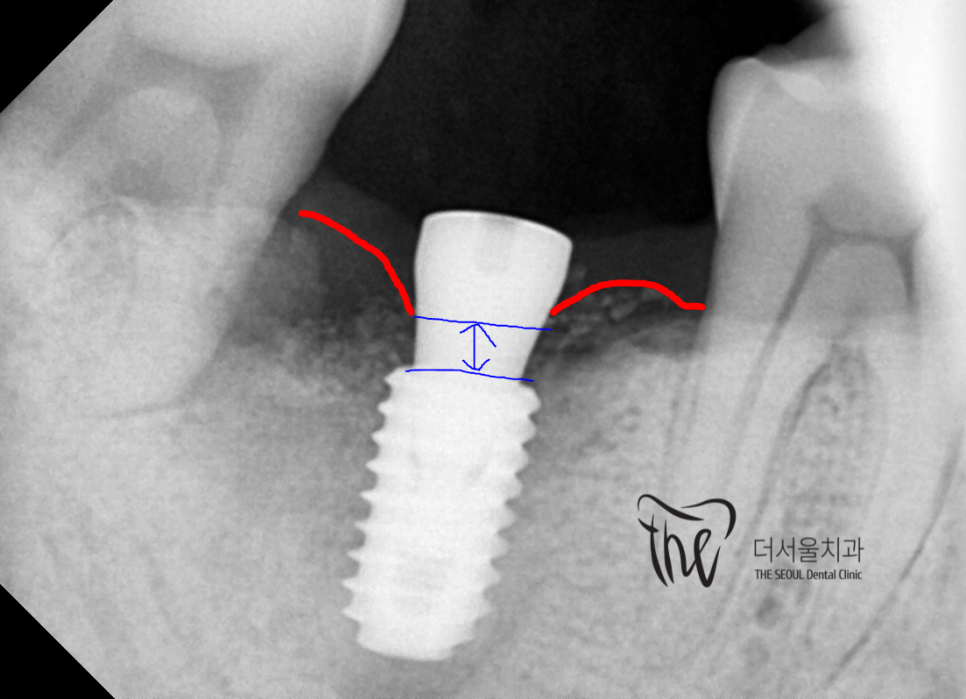

사전 진단 결과에 따라서, 예측 된 위치에

그대로 어금니 임플란트 를 심어드렸습니다.

적당히, 깊게 심어드린 것을 보실 수 있는데

충분한 교합력을 내려면 해상도 높은

방사선 사진에서 볼 수 있는것 마냥

Bone level 하방 1.5~2.0mm 에

심어줘야 됩니다.